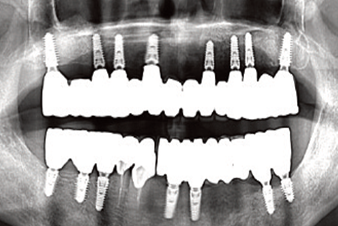

Clinical case: Full-mouth implants for mandibular & maxilla - restored using mixed prostheses

- Courtesy of Dr. Hyun Jun Kim, Korea -

Keywords

AnyRidge, full-mouth implants, mandibular, maxilla, edentulous, full mouth rehabilitation, Octa abutment, long-term clinical case, biological stability, Dr. Hyung Jun Kim

Products:

AnyRidge implant system